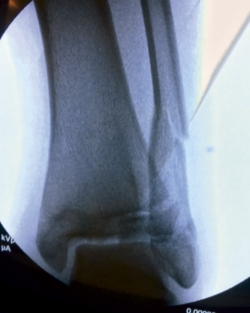

Se trata de un varón de 13 años de edad que acude a urgencias tras sufrir una caída y con eversión forzada del tobillo jugando al fútbol. A la exploración, presentaba inflamación en todo el tobillo izquierdo (región anterior y ambos maléolos) sin déficit neurovascular. En la radiografía simple se observó una fractura epifisiolisis de tipo IV (Figura 1).

Bajo anestesia general se intentó la reducción cerrada de las fracturas, sin éxito (Figura 3).

Figura 3. Radiografía intraoperatoria después de reducción cerrada.